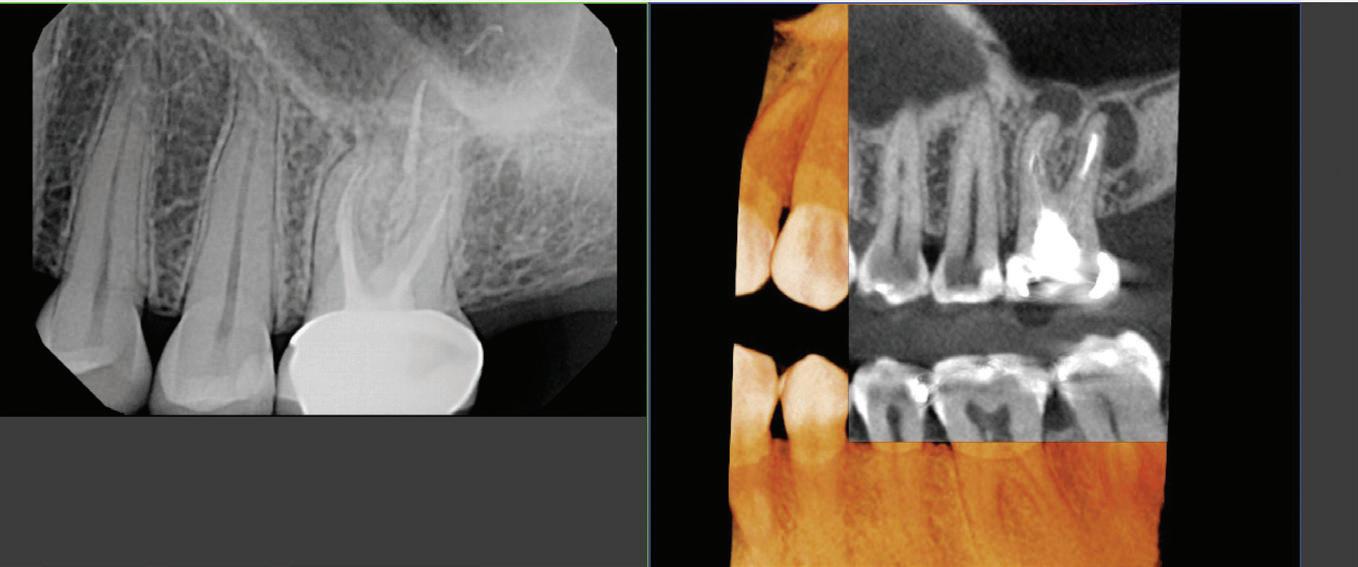

steel crowns, Acero Crowns was the first to make high-quality preformed stainless steel and esthetic crowns for children

“In pediatrics, everybody wants to use a precurved crown,” Park said. “When you’re treating a kid, you’ve got about a 15-20 minute window and even the best-behaved child is gonna start to lose their patience with you, so you have to be fast and efficient. And pre-curved crowns allow you to be fast so you can prep the tooth and then the crown just snaps right on . ”

The Acero stainless steel crowns come pre-formed and numbered, making it easier for doctors to identify and secure the crowns for young patients.

Acero Crowns evolved to manufacture more products, such as the Acero 3S Posterior crown line and the Acero ES resin-faced stainless steel crown line, to serve more patients .

Acero Crowns also produces the Acero Z1 zirconia line (top) and the Acero ES resin-faced stainless steel crown line (bottom) to help provide the look of a natural tooth .